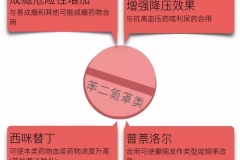

健康科普:6問催眠藥-會產(chǎn)生依賴嗎?哪些人不能吃?

健康科普:6問催眠藥-會產(chǎn)生依賴嗎?哪些人不能吃?

科普中國-樂享健康作者:李潔璇 長春市第六醫(yī)院 副主任藥師